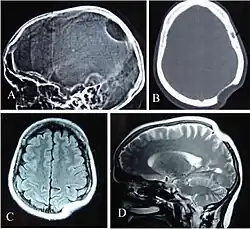

La maladie de Gorham-Stout est une ostéolyse spontanée et massive à l'origine d'une résorption progressive de l'os. C'est une maladie rare d'étiologie inconnue qui se manifeste le plus souvent chez l'enfant ou le jeune adulte[1]. Elle se caractérise du point de vue histopathologique par une prolifération des canaux vasculaires à paroi mince dans l'os[2].